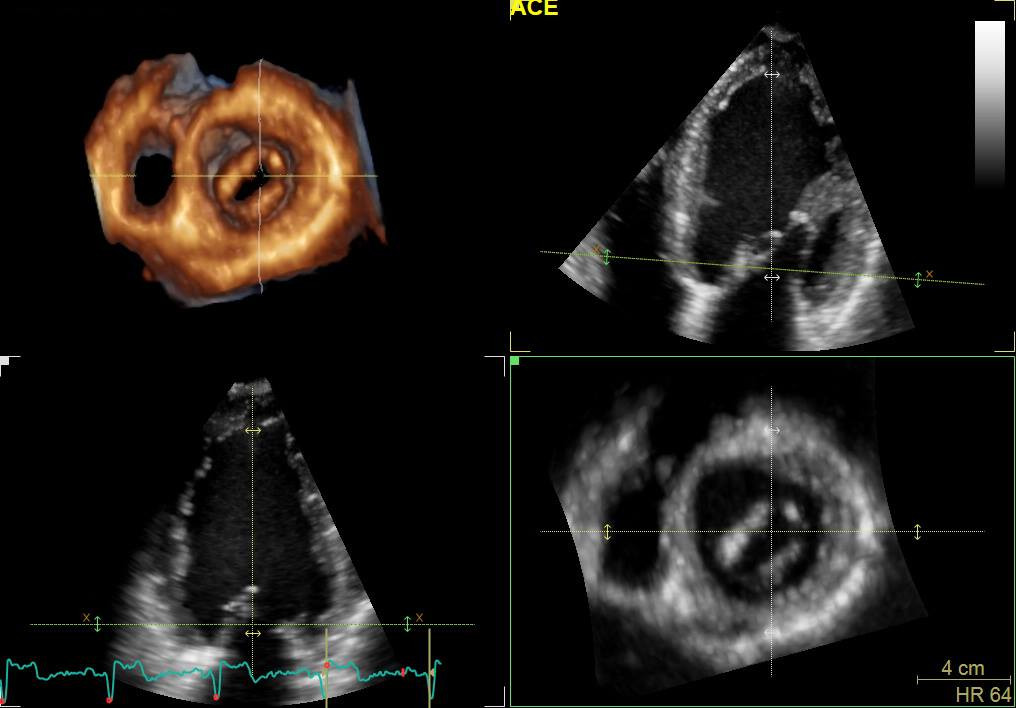

UNIDAD DE CARDIOLOGIA Y DE IMAGEN CARDIACA NO INVASIVA

• Ecocardiografía (estudios diagnósticos no invasivos)